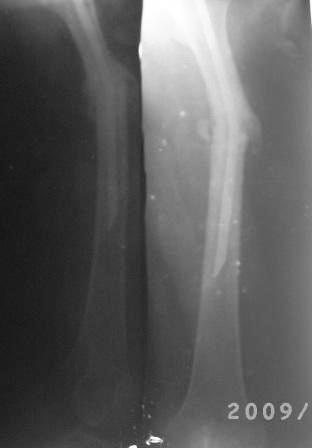

Уважаемые коллеги! Обратилась б-ная 1982г.р. 2008г. в апреле оперирована в одном солидном мед.учреждении, и/м остеосинтез штифтом лев.бедра( похоже Кюнчером), в то время была беременной, через месяц выкидыш. Со слов около 6 мес. коксит.гипсов. повязка,и до сих пор ходила с двумя костылями, кормили многими лекарствами как остеогенон. бонвива и мн. другими и даже гормонами. поправилась на 15-20кг. Но активно ногу могла поднять на 4 пальца от пола и не надолго.01.02.09.г упала на правую бок, с тех пор резкая боль в обл бедра, боиться шевелить ногой, не дает пальпировать,обратилась к леч.врачу, предлагали костно-пластическую операцию , после обратилась к нам. При тщательном исследовании выясняется что все таки имееться положительная динамика, боли уменьшается, при отвлечении можно двигать ногами, признаков рефрактуры нет, умеренная равномерная отечность, боли в мягких тканях, в надвертельной обл. боли нет, конец штифта не прошупивается. Мышцы бедра атрофированы, слабые. И на Р-гр я не вижу рефрактуру! Мой план, покой, анальгетики, УВЧ, антидепрессанты, после активация, пусть походить костылями потом без оних, реабилитация. После польной восстановлении решить вопрос удалении штифта. В отд. идет дискуссия по поводу рефрактуры, и о удалении штифта. Уважаемые коллеги помогите советом! С уважением Абдурашид.

Даже на такой "микро" рентгенограмме видна угловая деформация. В чем проблема сделать снимок бедра на всем протяжении? Боль, скорее всего,

Да, на Р-грамме имеется угловая деформация бедра и искривление штифта, но клинически оно мало заметно,в обл. деформации подвижность

не определяется, укорочение 1,0-1,5 см, б-ная очень нервозная, капризная (обычно таким б-ным что-то "умное" делать боишься -авось!), и ряд других факторов , подумал может, все обойдется более экономным методом.

Оставить на потом нельзя, попробую закрытую остеоклазию с коррекцией деформации и искривлении штифта (оказалось штифт Еланского для голени- где нашли и почему?), удалении из надвертельной обл,

рассверливание и реостеосинтез блокируюшим гвоздем статически, может,

ч-з месяц другой динамически. и по возможности ранняя активация.